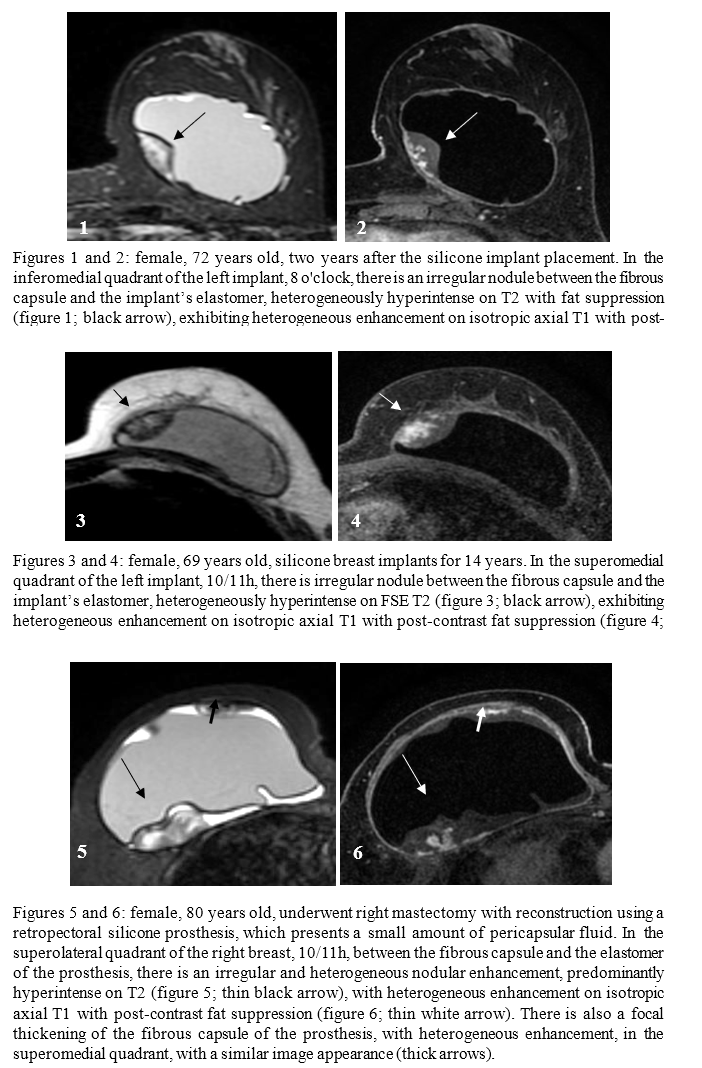

The hypothesis for SIGBIC diagnosis was based on imaging findings, which included the presence of a nodule between the elastomer and the fibrous capsule, exhibiting a heterogeneous and/or hyperintense signal on T2-weighted sequences, progressive contrast enhancement and hypointensity on T1-weighted sequences, as demonstrated in Figures 1 to 4. In addition to these findings, two patients showed a small amount of pericapsular collection, along with thickening and enhancement of the fibrous silicone capsule. Only one patient presented both a small pericapsular collection and focal thickening of the fibrous capsule simultaneously, as shown in Figures 5 and 6. Interestingly, the nodule and focal thickening had similar imaging characteristics, which supported the SIGBIC diagnosis. None of the cases showed capsular contracture or intra- or extracapsular rupture.